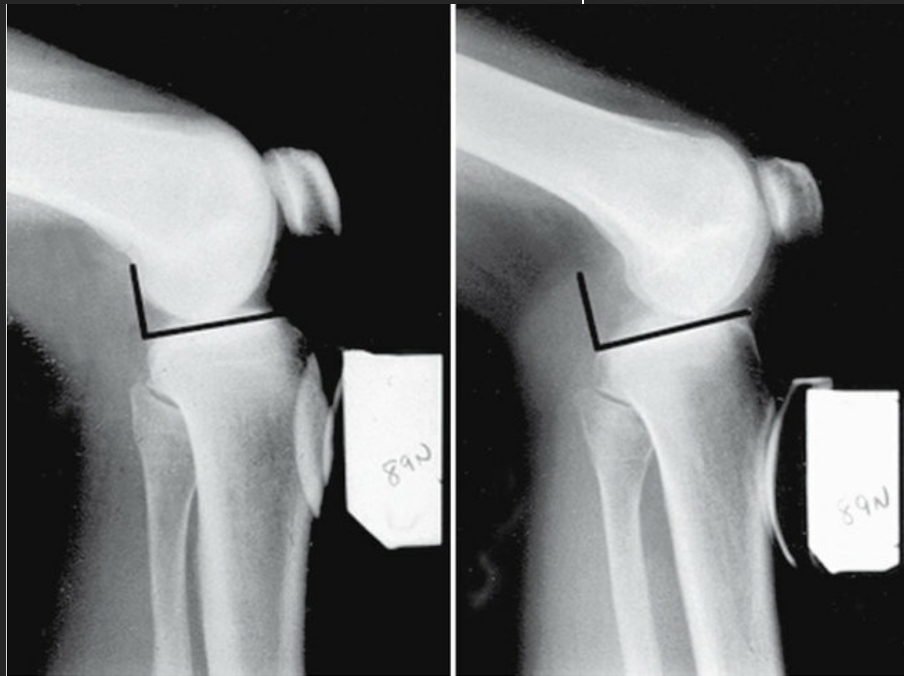

Primeiro exame de imagem solicitado nos casos de Lesão do LCP

A

RX com stresse

How well did you know this?

Função da radiografia com Estresse

Diferenciar entre lesões parciais e lesões completas do LCP. No caso de lesões completas, haverá uma posteriorização da tíbia > 10 mm